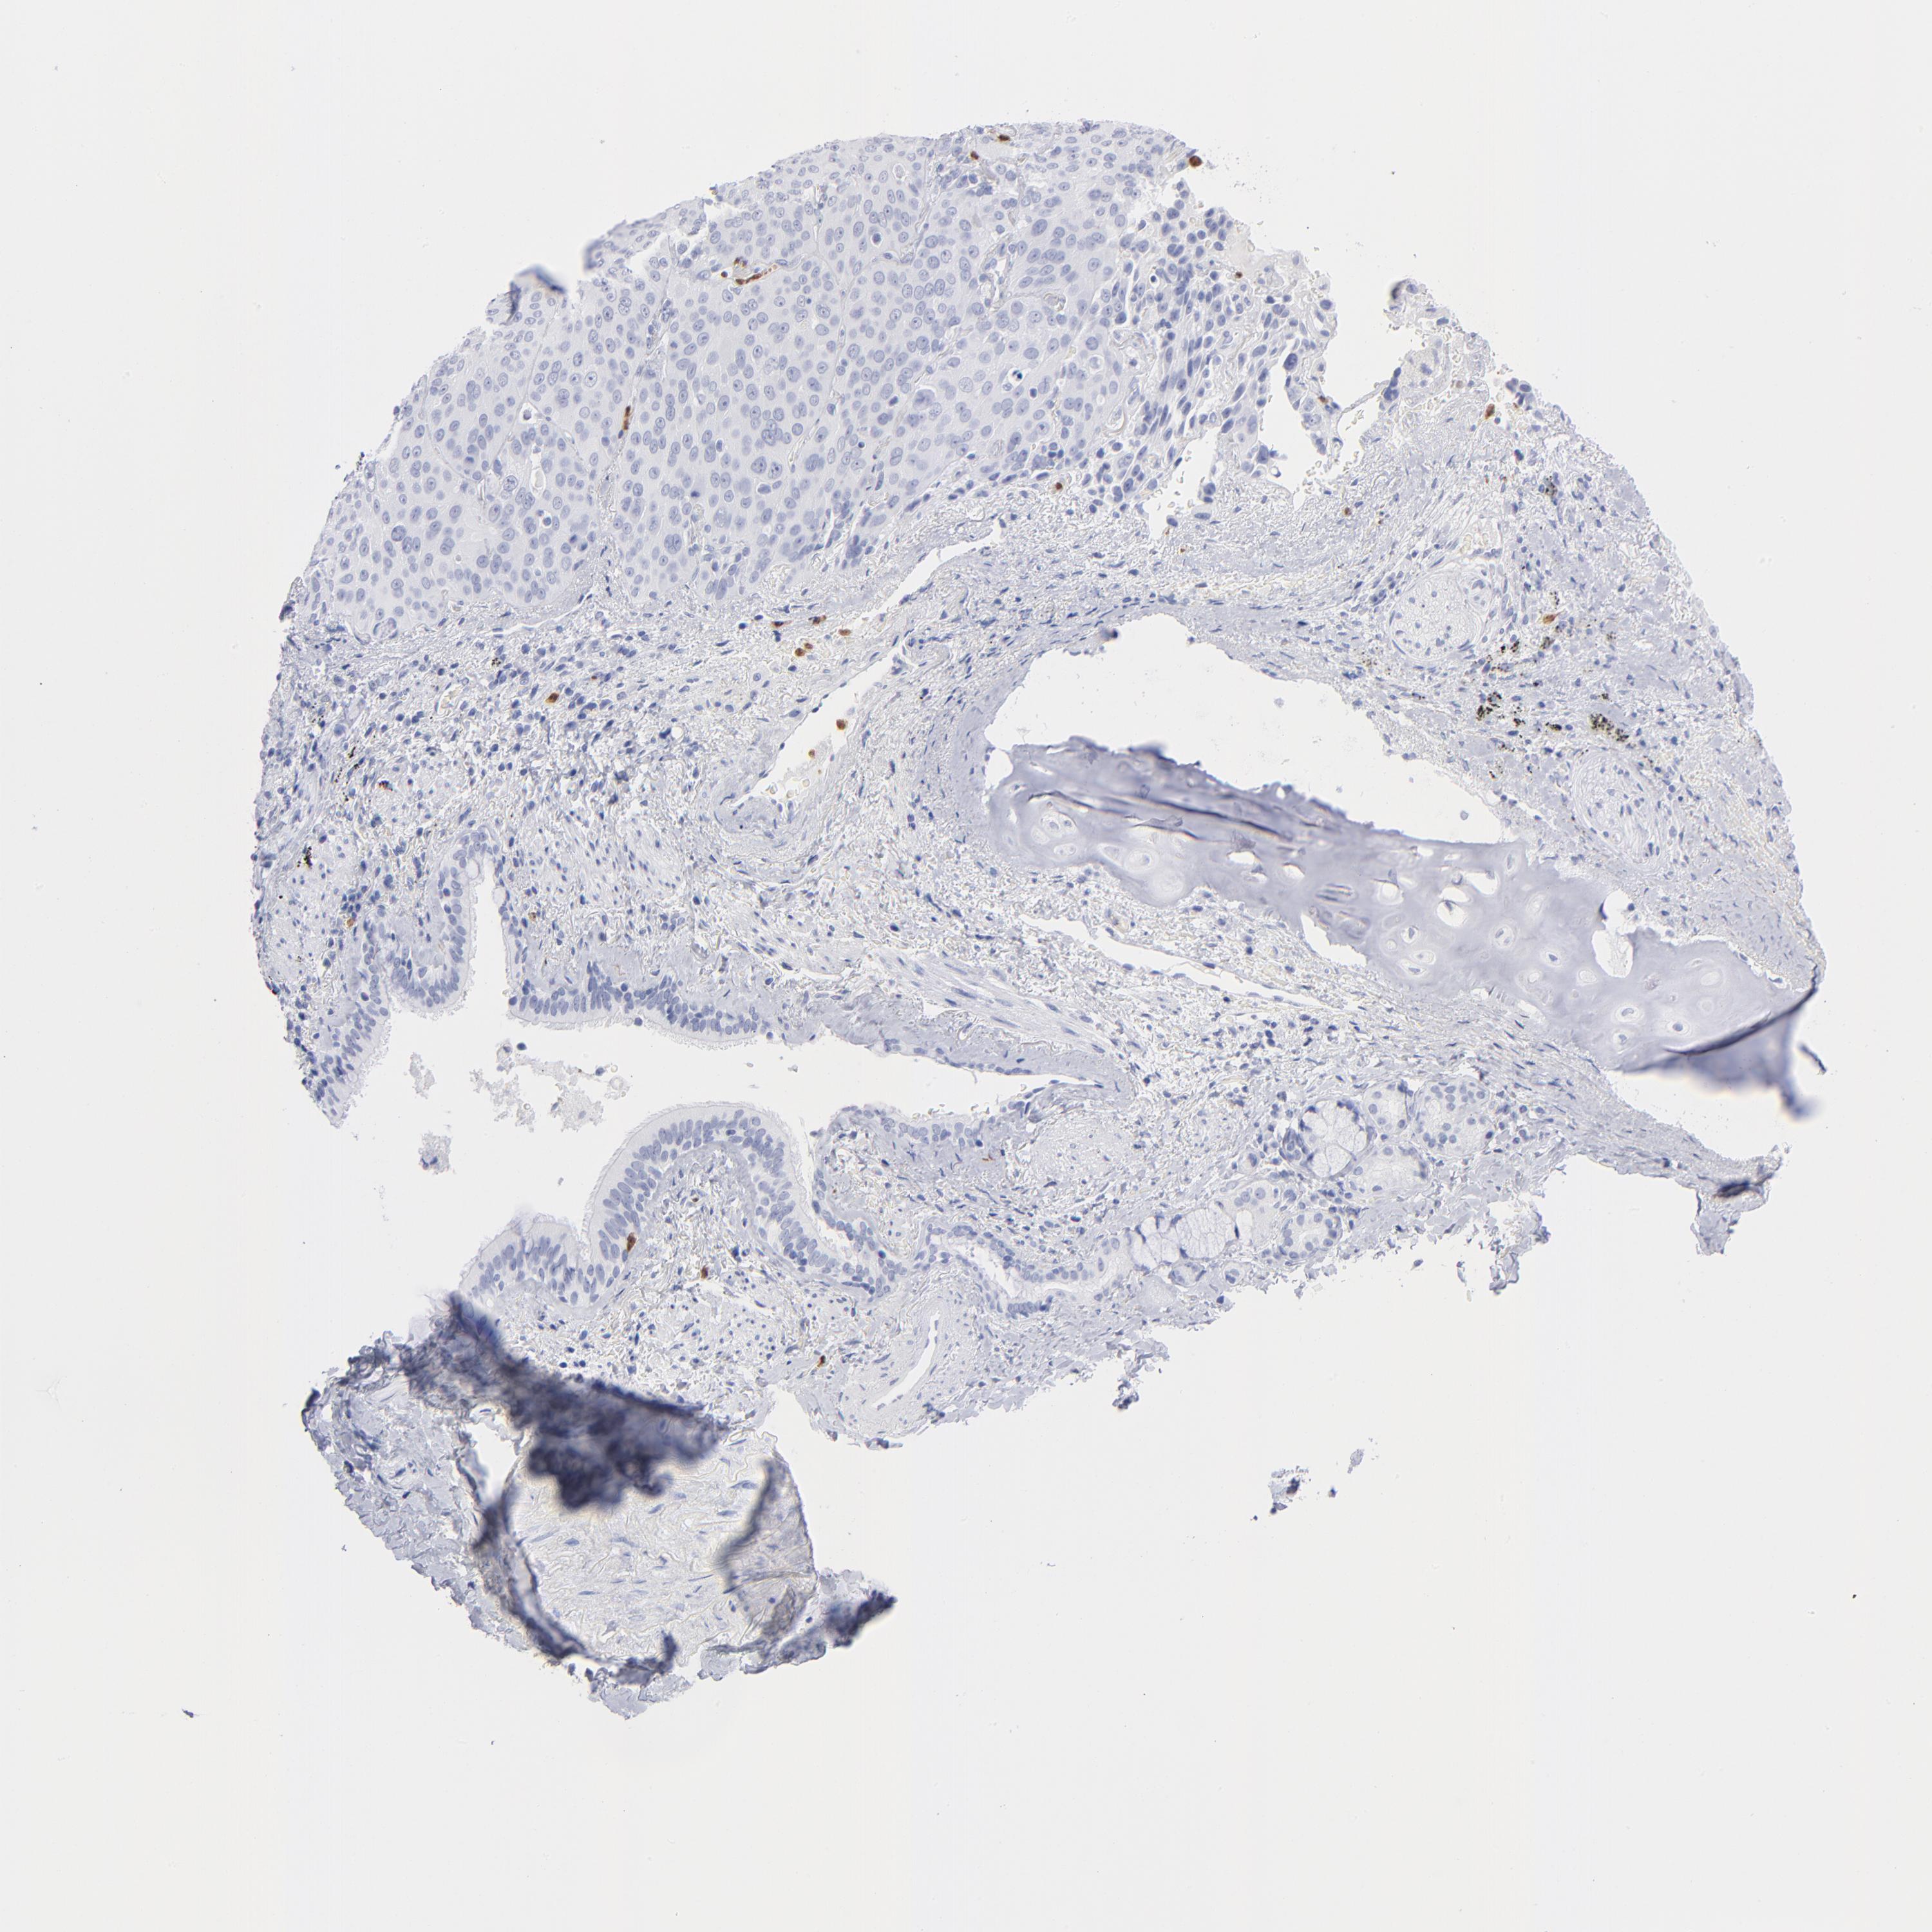

CANCER LUNG CANCER Show tissue menu

Lung cancer

Human cancer

ARG1 is not prognostic in Lung Adenocarcinoma (TCGA)

ARG1 is not prognostic in Lung Adenocarcinoma (validation)

ARG1 is not prognostic in Lung Squamous Cell Carcinoma (TCGA)